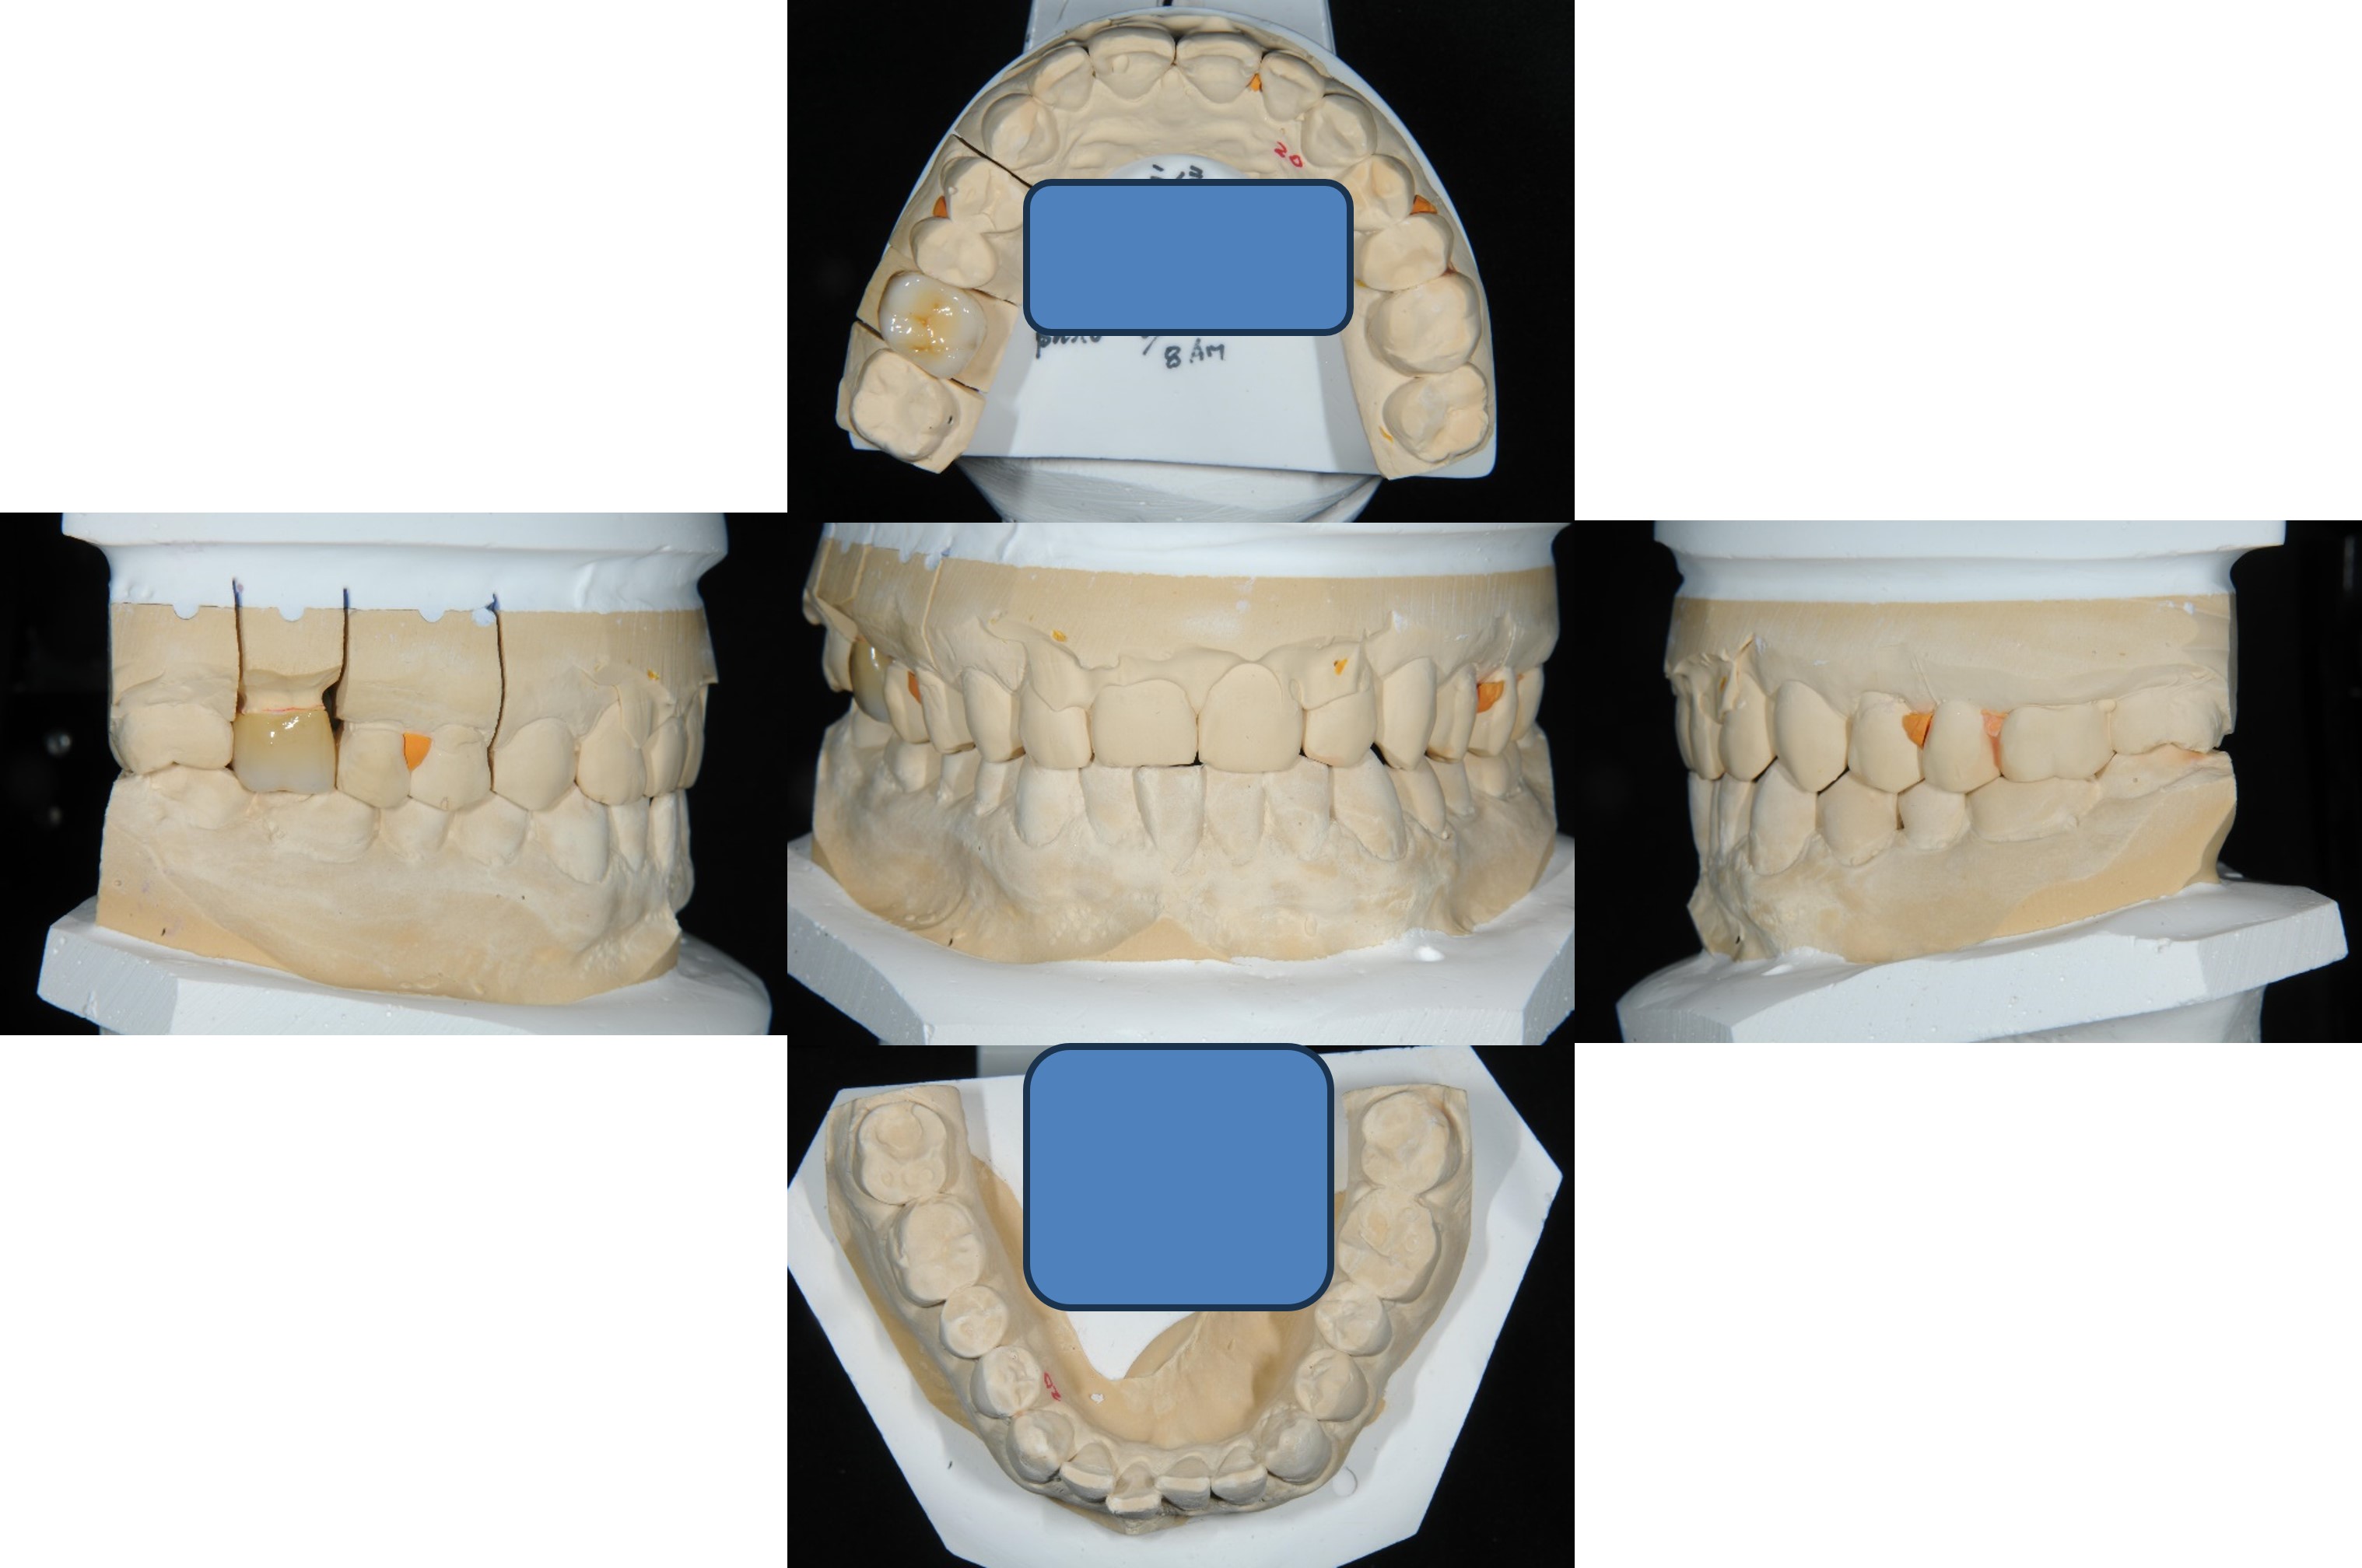

上面弓、上咬合器

技師於咬合器製作全瓷冠